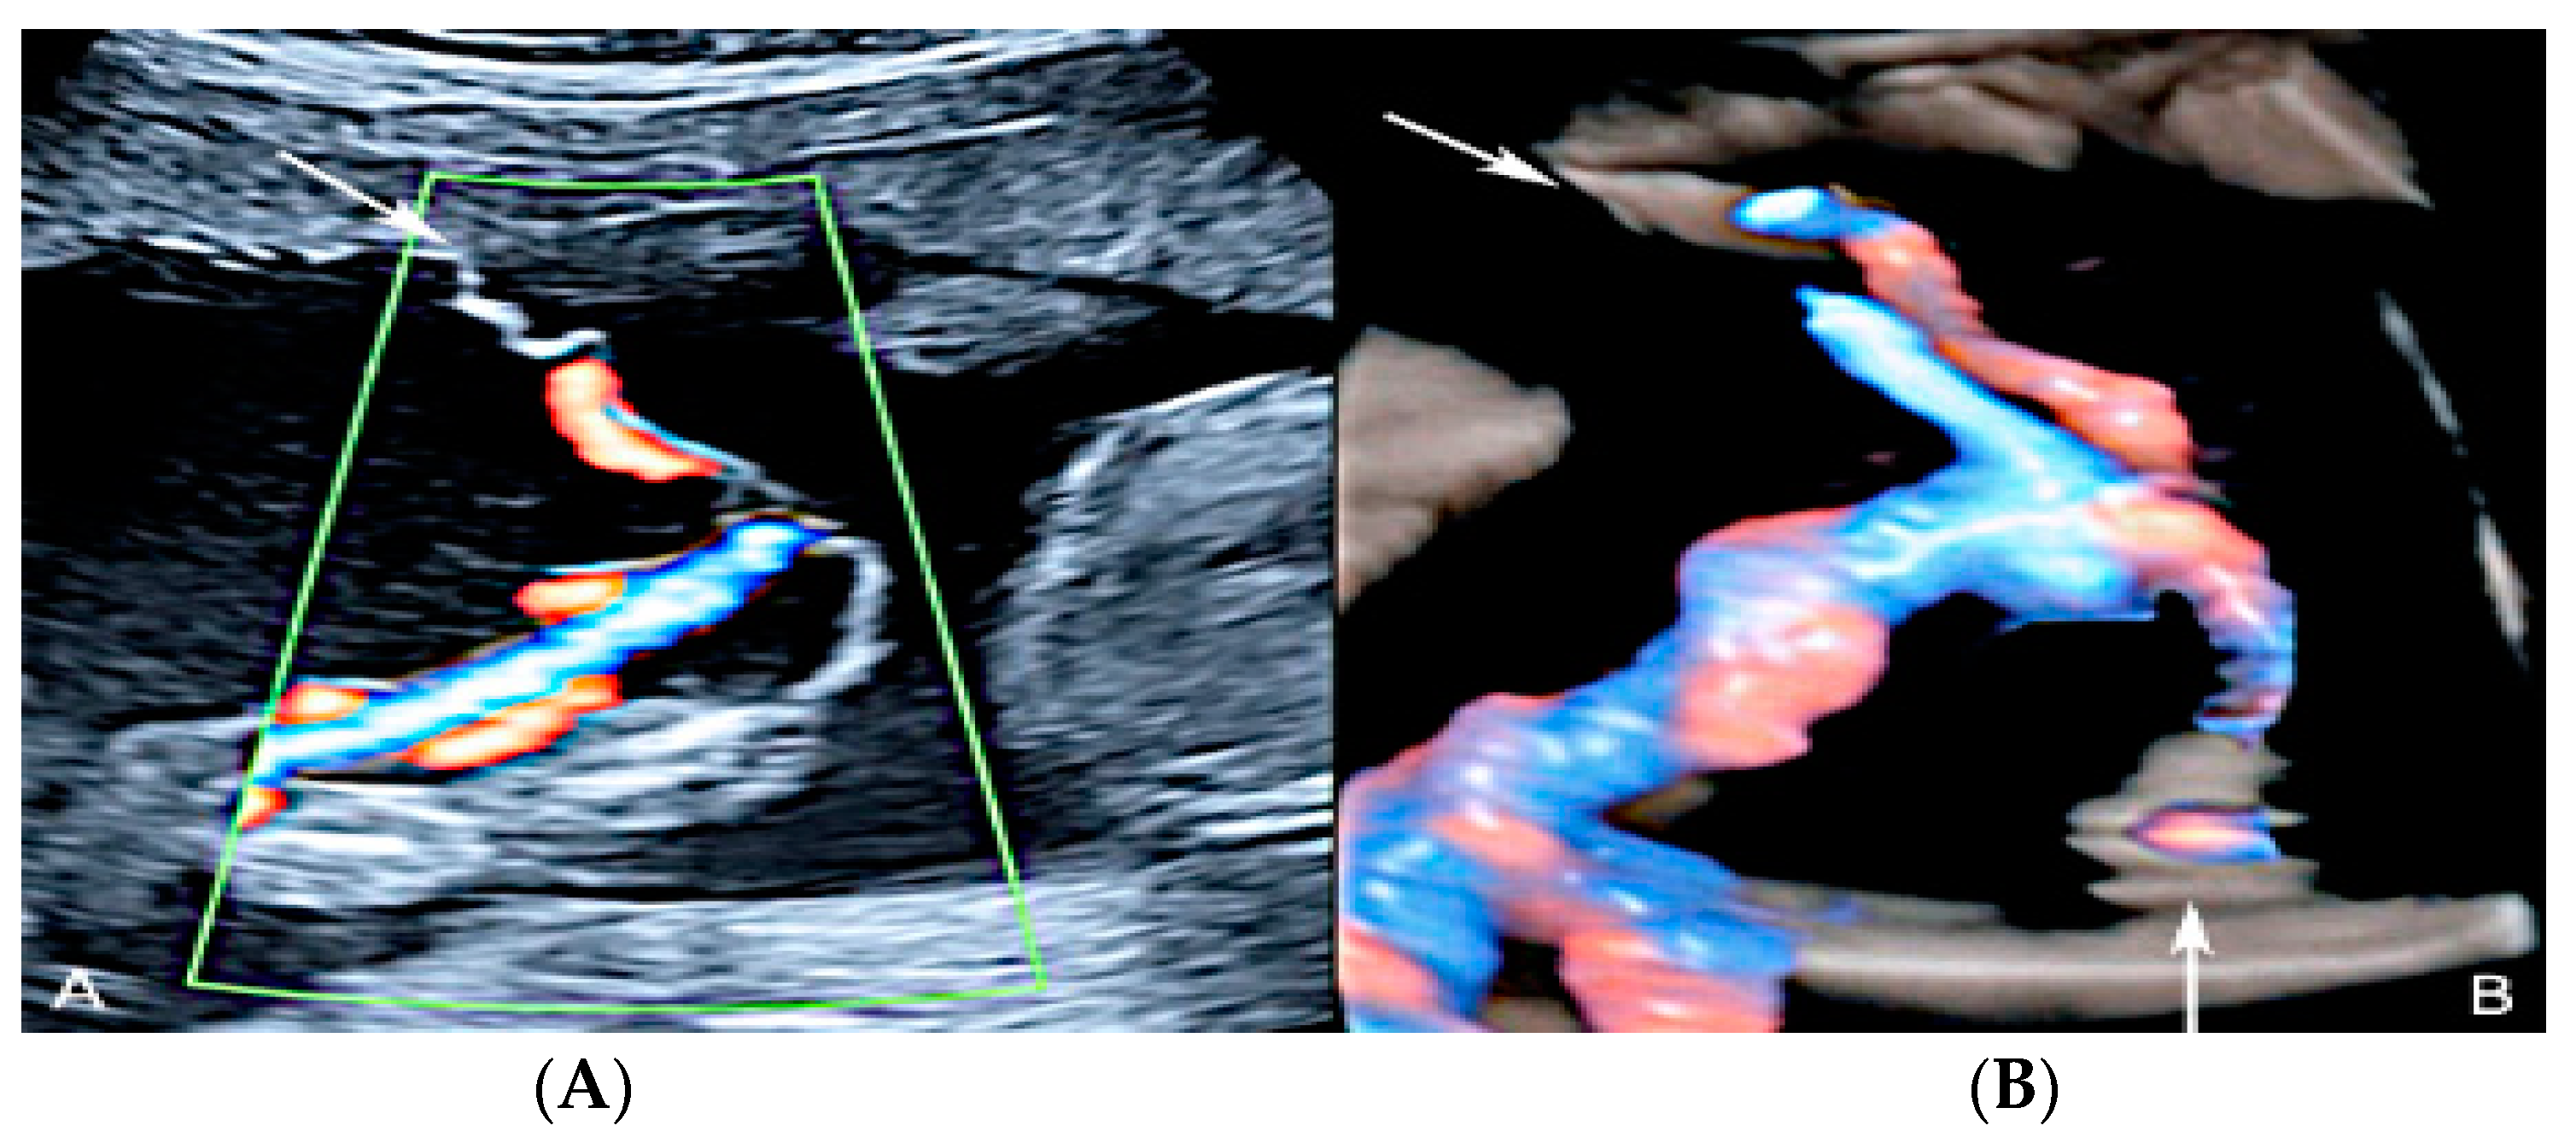

3.2.5. Furcate Umbilical Cord Insertion

3.2.6. Umbilical Cord Entanglement